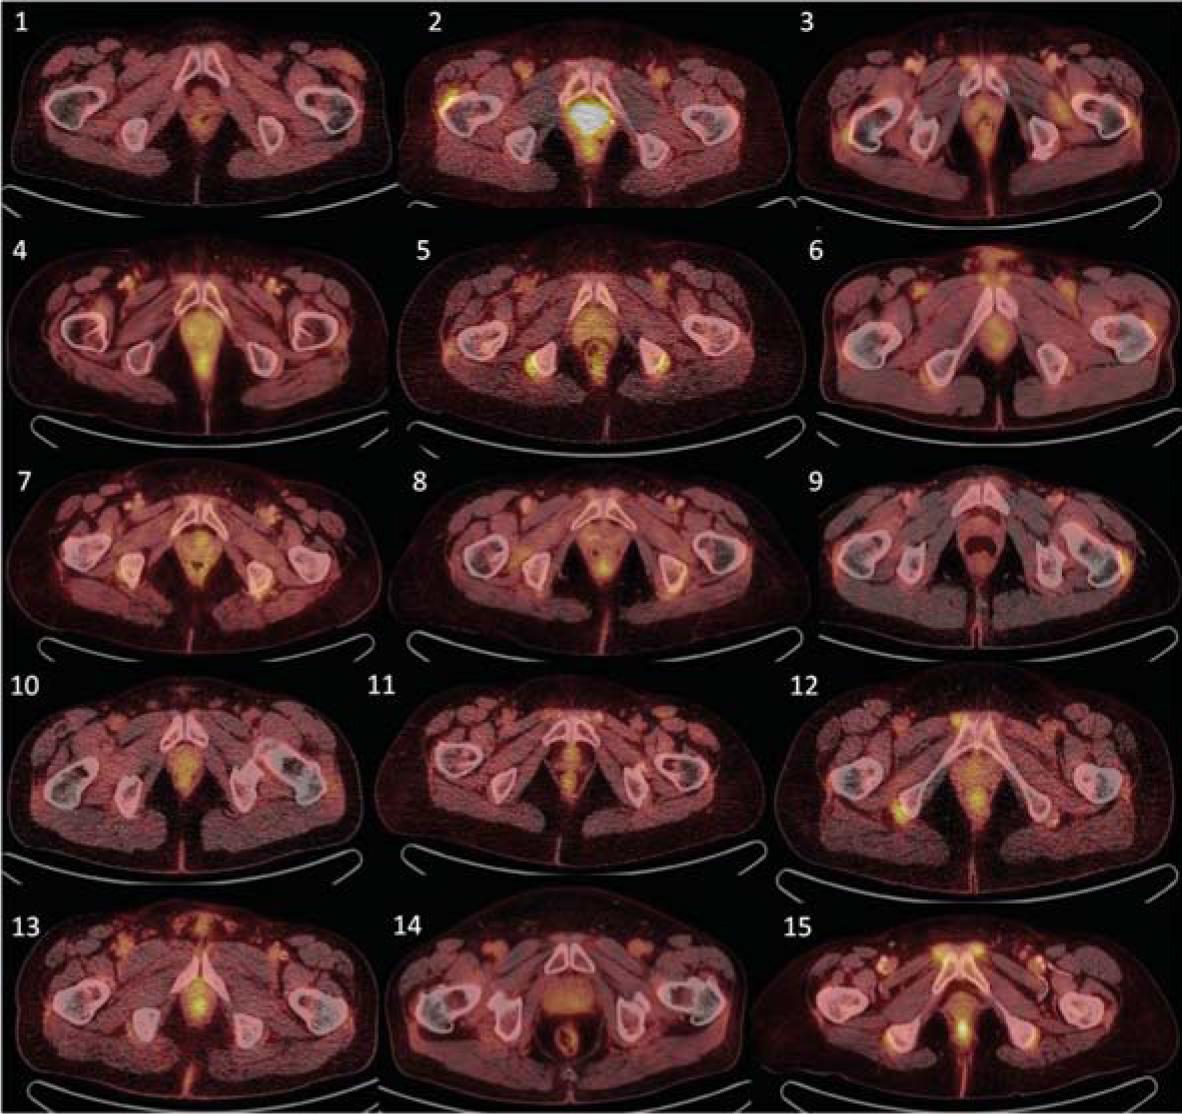

Given the retrospective nature of this study, it was not possible to keep a strict interval between baseline and follow up 18F-FDG PET/CT scans. Follow up examinations were timed by clinical purposes rather than by experimental needs. Follow up 18F-FDG PET/CT (median time 8 months, range 3-49) revealed continuing positivity around the shoulder girdle in only 2/15 patients, around hip joints in 3/15, around the sternoclavicular joint in 2/15, in extraarticular synovial structures in ischiogluteal bursae in 1/15 and in interspinous regions of cervical vertebrae in 1/15 patients. In three out of 15 patients, positivity in continuous large vessels was observed, maximally in 3 vessel regions out of 6 measured. In all evaluated locations in all analysed patients, a decrease in 18F-FDG accumulation (target-to-liver ratio) was observed, and no new positivity was indicated, including periarticular, extraarticular tissues or target large vessels. Praepubic accumulation of 18F-FDG was diminished in all patients after treatment with steroids. Praepubic-to-liver ratio was lower than 1.0 post therapy and this decrease in accumulation was clear by visual assessment (Figure 2).